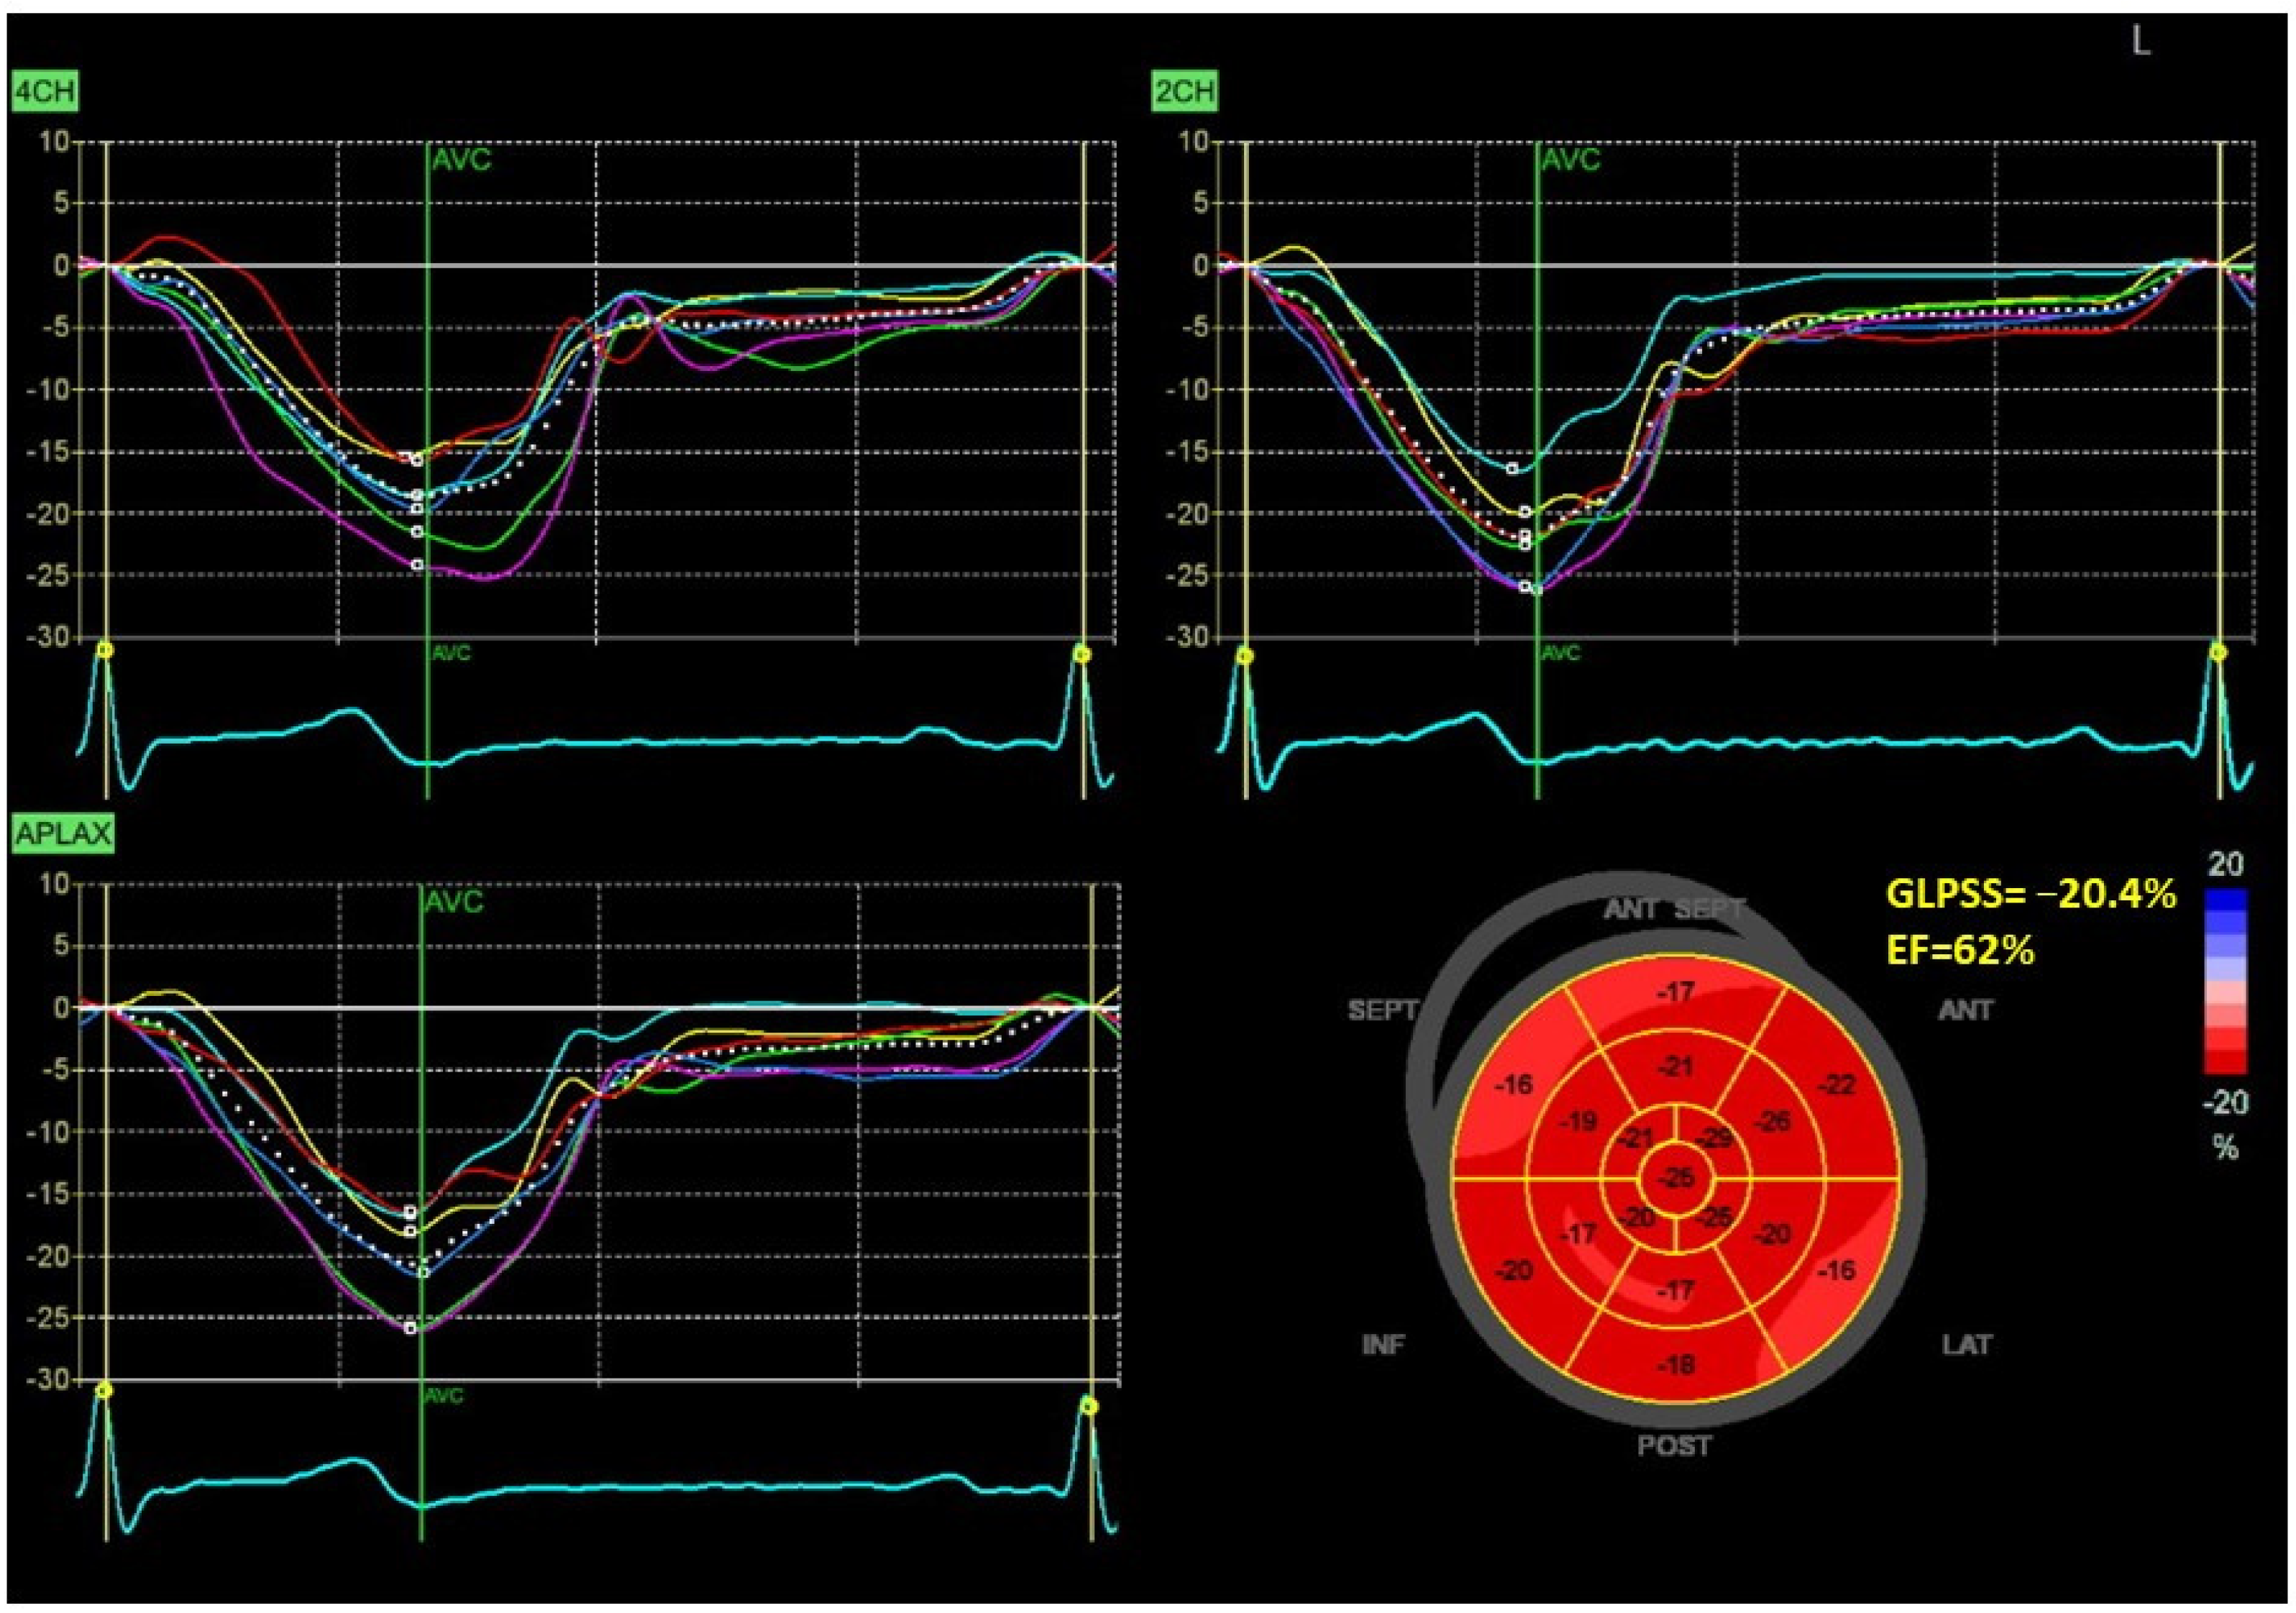

Figure 1 and Figure 2 show two contrasting examples (a healthy person and a patient after myocardial infarction and left bundle branch block) of STE curves with GLPSS, LVEF and LV pressure–strain loops and results of GWE for all LV segments.

Figure 1.

An example of echocardiography of a 30-year-old healthy male. A set of individual longitudinal strain curves for all segments shown in different colors, with the average curve shown as a white dotted line, a bull’s eye of segmental longitudinal peak systolic strains and a summary of global longitudinal peak systolic strain (GLPSS) are shown in the top panel. The LV pressure–strain loop with the bull’s eye representation of myocardial work efficiency for each of the segments and a summary of all myocardial work indices are shown in the lower panel. Abbreviations: GLPSS—global longitudinal peak systolic strain, EF—ejection fraction, GWI—global myocardial work index, GCW—global constructive work, GWW—global wasted work, GWE—global work efficiency, BP—blood pressure.